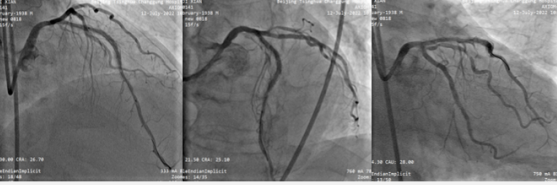

首先行LCX介入治疗,植入1枚支架。支架术后。(图3

图3 回旋支(LCX)支架术后